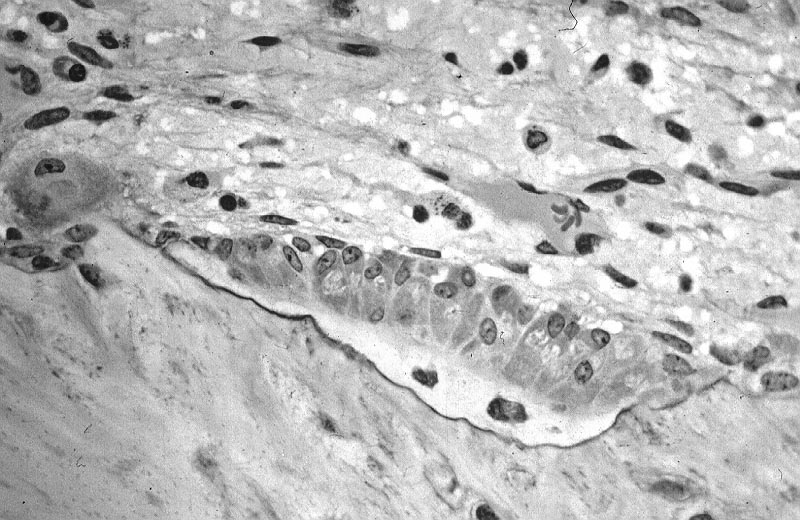

Histology of Paget disease of the bone reveals a mosaic pattern of lamellar bone.